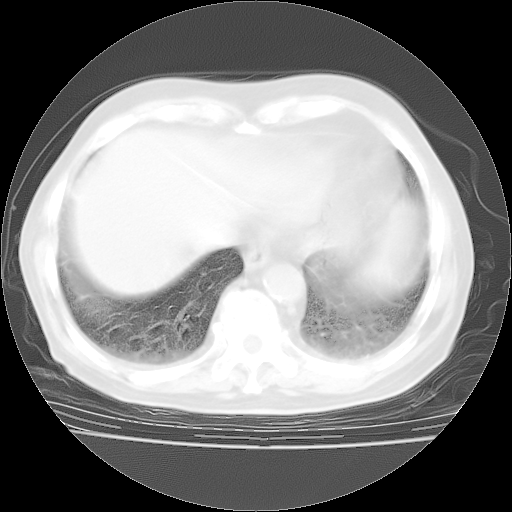

4月28日肺部CT——再次出现类似去年5月9日——透光度降低,“间质性”改变。

个人阅读4.14日肺部CT平扫:纵隔窗无异常,但肺窗示:双下肺内、后基底段有片絮状侵润影,部位以后基底段为著,以间质改变为主,呈急性肺泡炎征像,和首次住院影像学有相似之处。仅是个人读片,明日请相关专家再读片哈。其它建议同上。

今请临免主任会诊后认为:4月14日胸部CT已有双下肺间质性改变。患者病情复发多系激素减量过快不正规所致。目前甲强龙80mg/日,一周后酌情开始减量,不易过快。环磷酰胺若已停用,暂不使用。他同意目前抗菌药物使用,但应考虑是否加用B-内酰胺类抗菌药物(中性细胞明显增高);2、结核复发目前依据不足;3、若免疫全套各项指标正常,考虑多系特发性肺间质炎可能大。4、加强支持,并注意保护胃黏膜。